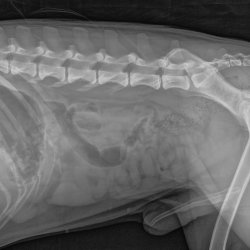

RTG snímek Rocky